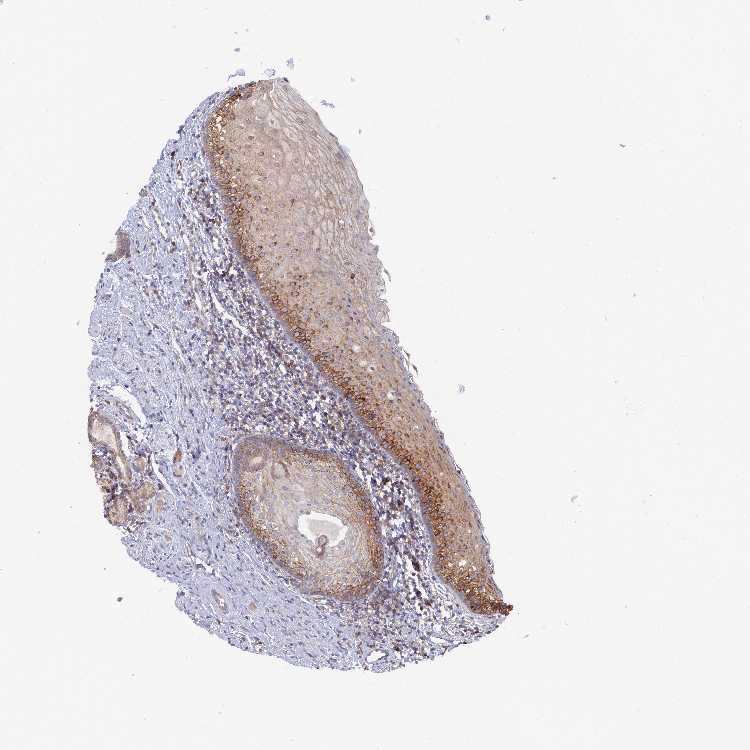

TISSUE PRIMARY DATA ORAL MUCOSA Show tissue menu

Oral mucosa

ORAL MUCOSA - Expression summary

Oral mucosai

On the top, protein expression in current human tissue, based on all annotated cell types, is reported with the units not detected (n), low (l), medium (m) and high (h). Underneath, protein expression in each annotated cell type are reported using the same units.

Protein expression data is based on knowledge-based annotation. For genes where more than one antibody has been used, a collective score is set.

ORAL MUCOSA - Antibody stainingi

Antibody staining in the annotated cell types in the current human tissue is reported as not detected, low, medium, or high, based on conventional immunohistochemistry profiling in selected tissues. This score is based on the combination of the staining intensity and fraction of stained cells.

Each image is clickable and will lead to virtual microscopy that enables deeper exploration of all samples and also displays staining intensity scores, fraction scores and subcellular localization as well as patient and tissue information for each sample.

Antibody HPA040304Antibody HPA057159Antibody CAB005875

Squamous epithelial cells HighHighHigh